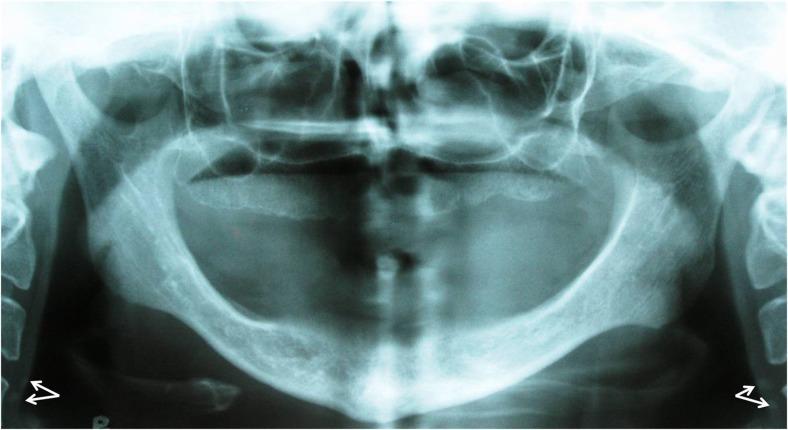

A total of 960 panoramic radiographs of patients above 40 years old were evaluated. Doppler Sonography (DS) was performed for patients who showed calcified carotid artery atheroma (CCAA) in panoramic radiogra-phy in order to determine the presence of CCAA and the degree of stenosis. Cardiovascular risk factors in both groups of patients with CCAA (12 subjects) and without CCAA (3 subjects) were compared using a questionnaire filled out by the patients. Statistical analysis including Fisher and independent t-test applied for data analysis.

Fifteen patients (30 sides) showed calcification in their panoramic radiographs, and underwent DS which revealed CCAA in 16 sides (12 patients). Two patients (13.33%) showed stenosis greater than 70%. Among the risk factors, only age showed a significant association with the occurrence of carotid calcified atheroma (P=0.026).